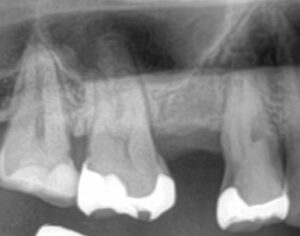

Before/After X線写真

治療前は根尖部に透過像(黒い影)が見られ、炎症が進行していました。

治療後は根尖の封鎖が確認でき、炎症の範囲が縮小しています。

X線比較により、根管内が適切に処置されていることを確認しました。